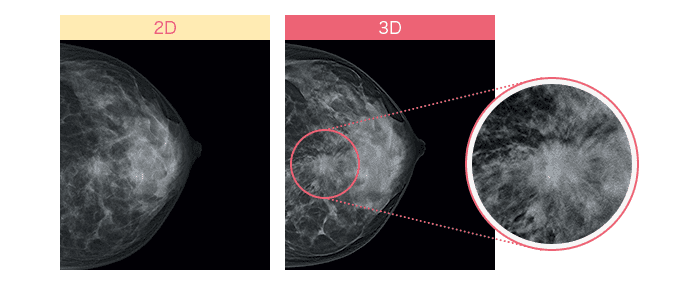

従来のマンモグラフィ画像は、平面の撮影(2D)のため乳腺と病変が重なると、判別が難しく正確な診断に時間を要することがあります。

しかし最近では乳房内の構造をより正確に描出できる「3Dマンモグラフィ(トモシンセシス)」が登場して、より高い精度で乳がん検査を行うことが可能になりました。異なる角度から乳房の画像を複数撮影し、それを再構成して乳房の断層像を生成することで、乳腺の重なりが除外でき、これまで発見が難しかった病変の観察がしやすくなりました。*4